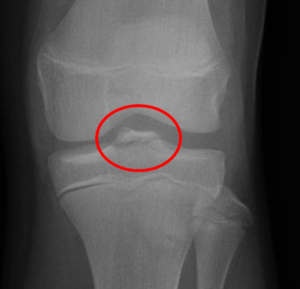

El diagnóstico de esta fractura se realiza mediante una radiografía de rodilla. Sin embargo, si la fractura es poco desplazada, puede no ser identificada en una primera evaluación, por lo que puede ser recomendable realizar un TAC o una resonancia de la rodilla.